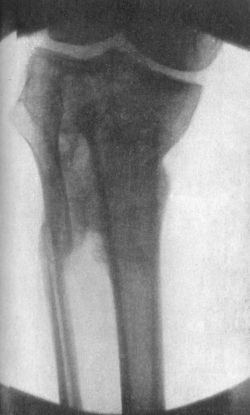

84.Radiogram of Fracture of Head of Tibia and upper Third of Fibula163

85.Radiogram illustrating Schlatter's Disease164